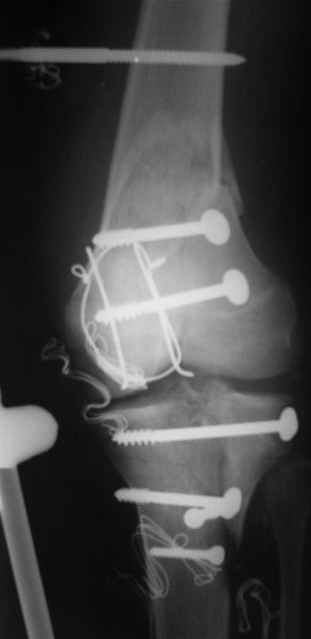

Re: открытый перелом мыщелков бедра, латерального

Вид раны на сегодня...

4 cутки после травмы.